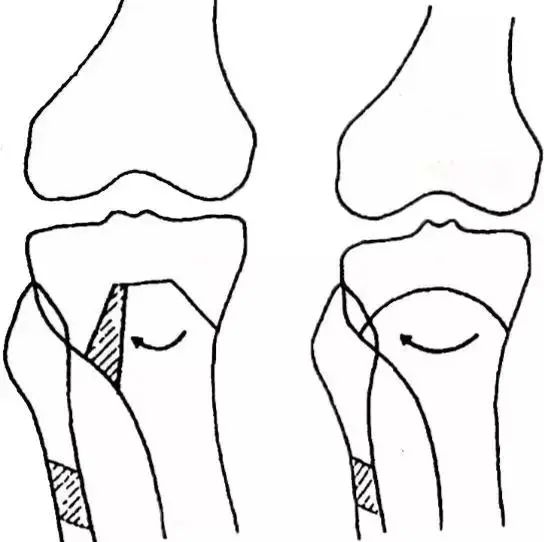

(a)、 闭合式楔形截骨术

多数学者愿意采用闭合式楔形截骨术,原因是开放式楔形截骨术需要植骨,因而延长术后制动时间,并有时可因植骨被吸收而导致矫正度丢失或延缓愈合。闭合式楔形截骨术虽使患者肢体稍有短缩,但截骨操作容易,截骨接触稳定。

(b)、半开放楔形截骨术当患者膝内翻畸形严重时,若行闭合式外翻楔形截骨术,切除楔形骨块较大,小腿短缩较多。

施行半开放楔形截骨术,可截除较小的楔形骨,矫正较大的内翻,即在胫骨上端外23做闭合式楔形截骨,内侧側13水平方向截断,然后将外侧截下的楔形骨块插入内13开放的楔形缺损中。

(半开放楔形截骨)

(c)、台形截骨术或倒“V”字形截骨术此法是在胫骨结节正上方做一水平横行截骨,两侧各做一斜行截骨,使之呈“台”字形。

在台形外侧根据矫正度大小截除骨块,然后将外侧截骨面闭合,而将外侧截下的骨块插入内侧开放后的间隙中,故台形或倒"V"字形截骨少有小腿短缩,可防止截骨端侧方错位,易于在术后对矫正度进行再纠正。但台形截骨术不利于内固定物的应用。

(台形截骨术)